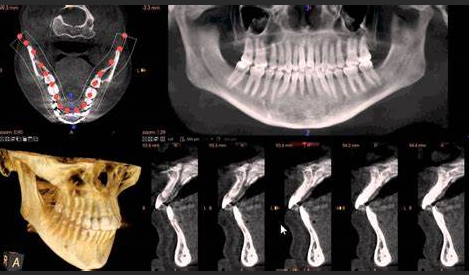

- Cone-Beam Computed Tomography (CBCT): CBCT offers 3D imaging capabilities, allowing clinicians to visualize the oral and maxillofacial structures in detail. This is crucial for implant planning, orthodontic assessments, and TMJ evaluations.

- Case Study 1: A patient with undiagnosed periodontal disease was evaluated using CBCT, revealing bone loss not visible on traditional X-rays. This early detection allowed for timely intervention, preventing tooth loss.